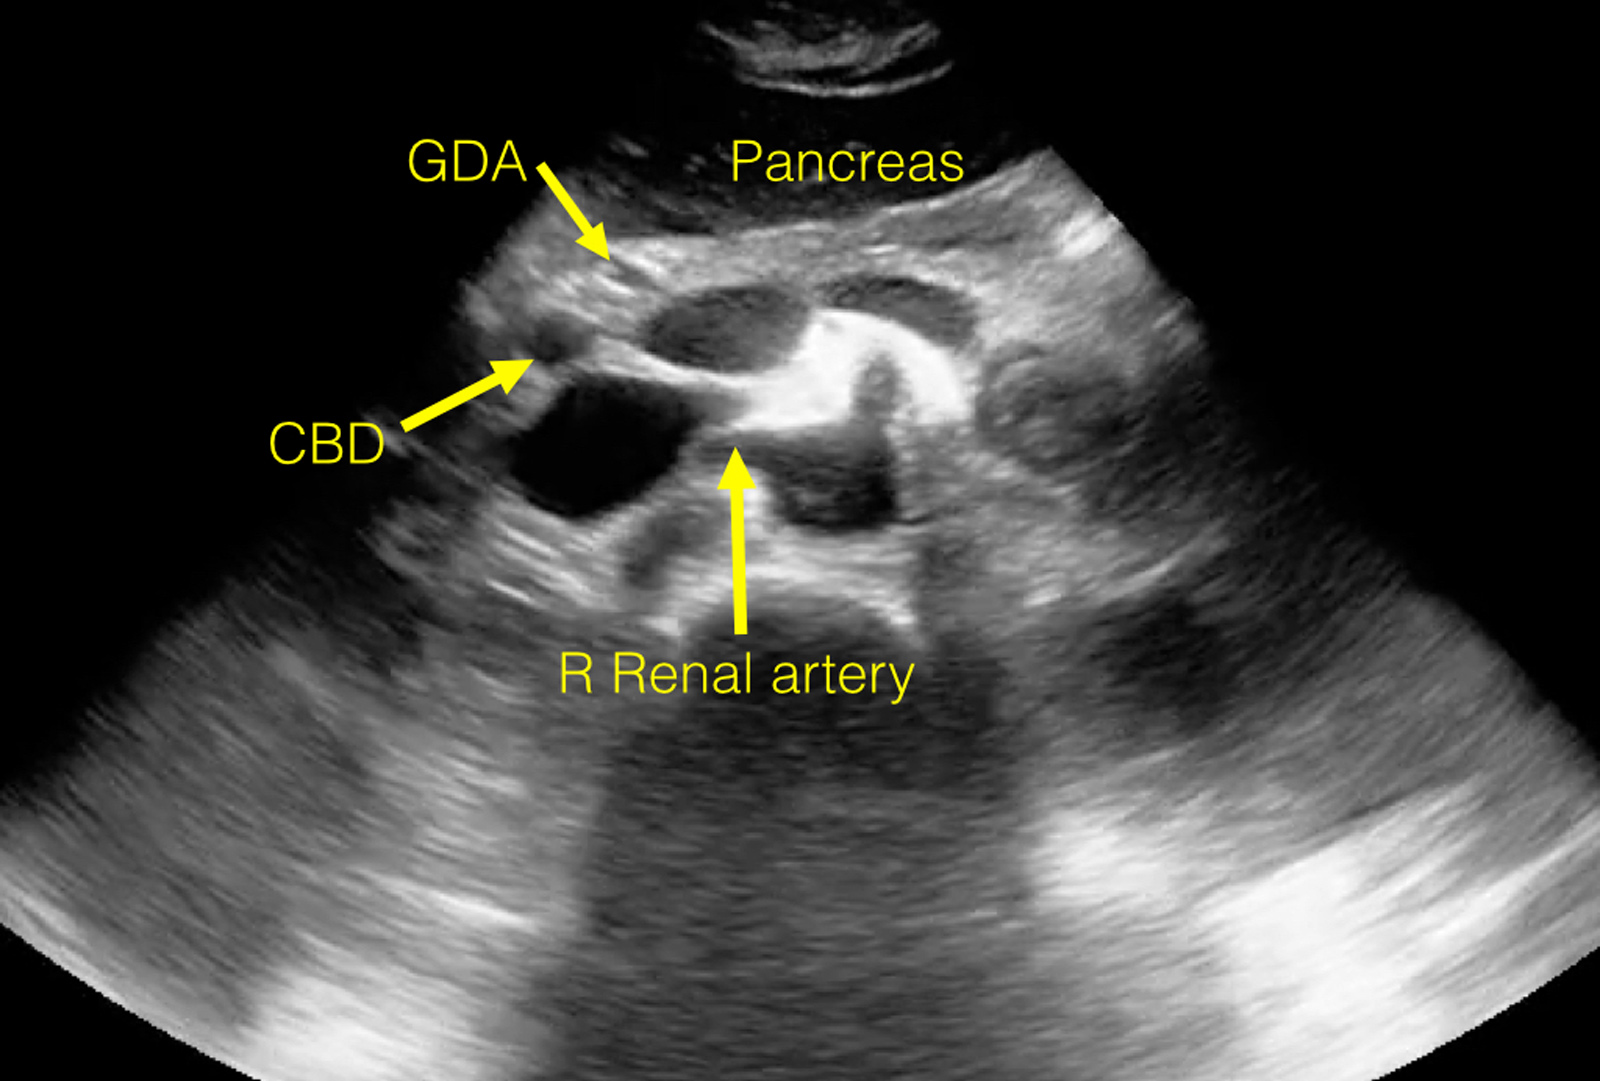

Anatomy Review—Proximal Aorta

View an ultrasound demonstrating the anatomy visualized during a routine study of the proximal aorta.

The following images are stills taken from the clip to identify the structures: